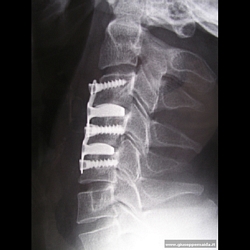

Ernie discali cervicali,microchirurgia e stabilizzazione

• In  casi biomeccanicamente"instabili",alla rimozione microchirurgica del disco intervertebrale patologico(ed erniato),segue una"stabilizzazione"vertebrale mediante sistemi con placche e viti in titanio o con "gabbie"(capitolo successivo):alcuni esempi